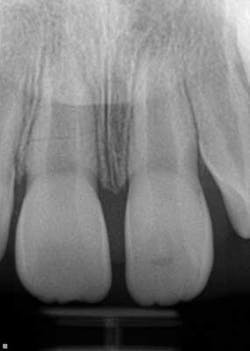

A healthy 7-year-old female presented directly from school with her father stating that she fell off the monkey bars. This was her first visit to the dentist. Initial exam revealed that tooth No. 8 was partially avulsed (Fig. 1) with only a slight attachment to the gingiva. All other teeth appeared clinically normal. Radiograph assessment revealed a large open apex on No. 8. The patient was given a local. The clot was removed and the area irrigated with a saline rinse. Next, the tooth was gently repositioned in the socket with slight compression of facial and lingual alveolar processes. A nonresilient wire splint was placed from NOs. 7 through 9. The patient was given an Rx of antibiotics for potential infection. A one-week assessment revealed a significant decrease of swelling with No. 8 appearing fairly stable. After eight weeks, tooth No. 8 had a slight delay to cold testing with all other teeth testing normal. The splint was removed. It was discussed with the father that the delayed response could be attributed to the healing of pulp or potential pathology. A two-month follow-up was recommended.